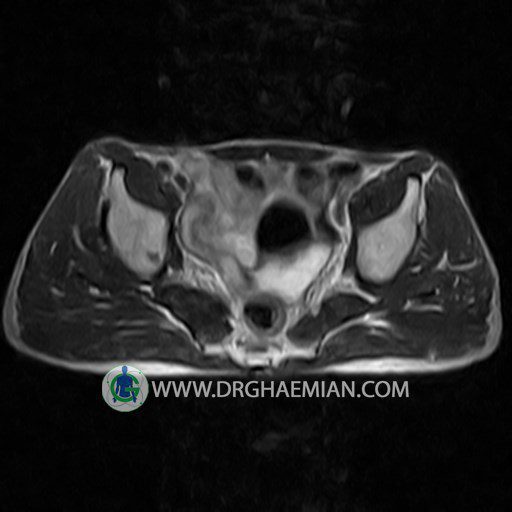

پزشکان اغلب از تصویربرداری ام آر آی برای تشخیص و درمان عارضه های پزشکی که فقط با استفاده از اشعه ایکس یا میدان مغناطیسی و امواج رادیویی قابل مشاهده است، استفاده می کنند. دستگاه ام آر آی تصاویر دقیق از ساختار های داخلی بدن ایجاد می کند. در این کیس استئومیلیت لگن، آتروز و سنیویت دیده می شود.

HIP JOINT MRI

( without contrast )

Technique : coronal STIR , coronal T2 , Axial T1 , axial T2 .

REPORT:

The femoral heads and acetabula are normal shape , signal intensity and the femoral heads are well covered by the acetabular margins .

The joint spaces are of normal width without fluid collection .

The articular surfaces are smooth and congruent and show normal cortical thickness .

– Heterogeneous signal change (high T2/STIR , low T1) in proximal metaepiphysis of left femur without articular surface irregularity suggestive for bone bruise (stress fracture?), osteomyelitis & arthritis and marrow infiltration (less probable)

– Left hip joint effusion suggestive for synovitis

are seen.

COMMENT: Clinical correlation and MRI with contrast are recommended.